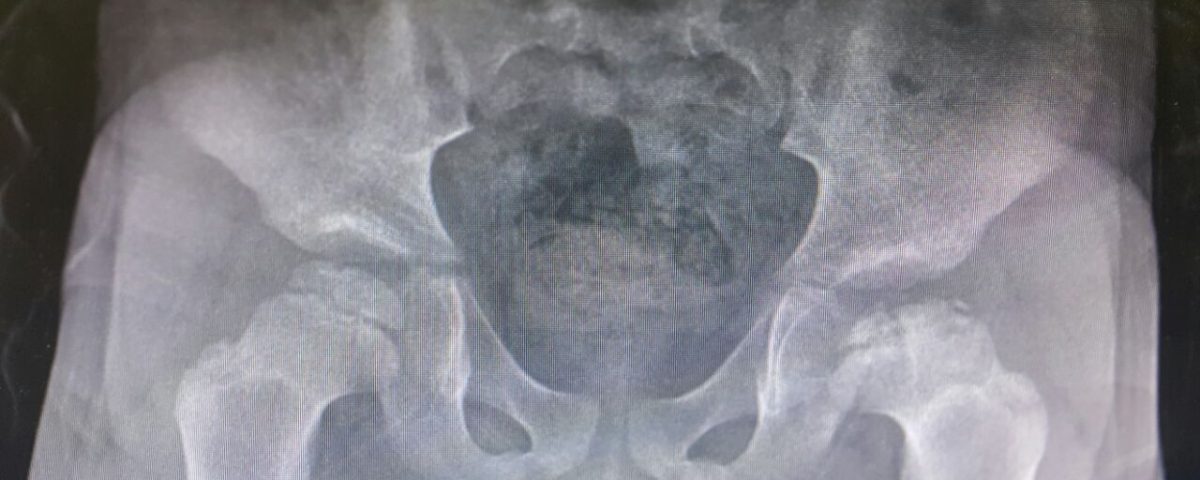

Legg-Calvé-Perthes hastalığı tanımlanmasının üzerinden bir asır geçmiş olmasına rağmen gerek etiyolojisinin tam olarak

aydınlatılamamış olması gerekse tedavisi üzerinde fikir birliğinin oluşmaması nedeniyle gizemini halen korumaktadır.

Perthes hastalığı femur başı epifizinin avasküler nekrozu olarak tanımlanabilir. Çocukların yeniden şekillenme kapasitesinin yüksek oluşu nedeniyle yetişkindeki benzerinden farklı seyreder. Hastalığın seyri boyunca her hastanın farklı

değişkenlere maruz kalması nedeniyle, neredeyse hastalığın her hastada farklı şekilde seyretmesine neden olur. Bu durum standart tedavi protokollerinin geliştirilmesinin önünde engel teşkil eder. Tedavinin temel amacı femur başı küreselliğinin ve asetabuler uyumun hastalıktan en az düzeyde etkilenmesini sağlamaktır. Bu hedefi tutturmak için genel kabuledilen görüş femur başının asetabulum içinde tutulmasını sağlamak, bu sayede asetabulumun femur başını şekillendirmesini temin etmektir. Perthes hastalığında örtünme prensibinin uygulanması temel tedavi yöntemidir. Örtünme prensibi ya konservatif ya da cerrahi yöntemlerle sağlanabilir.